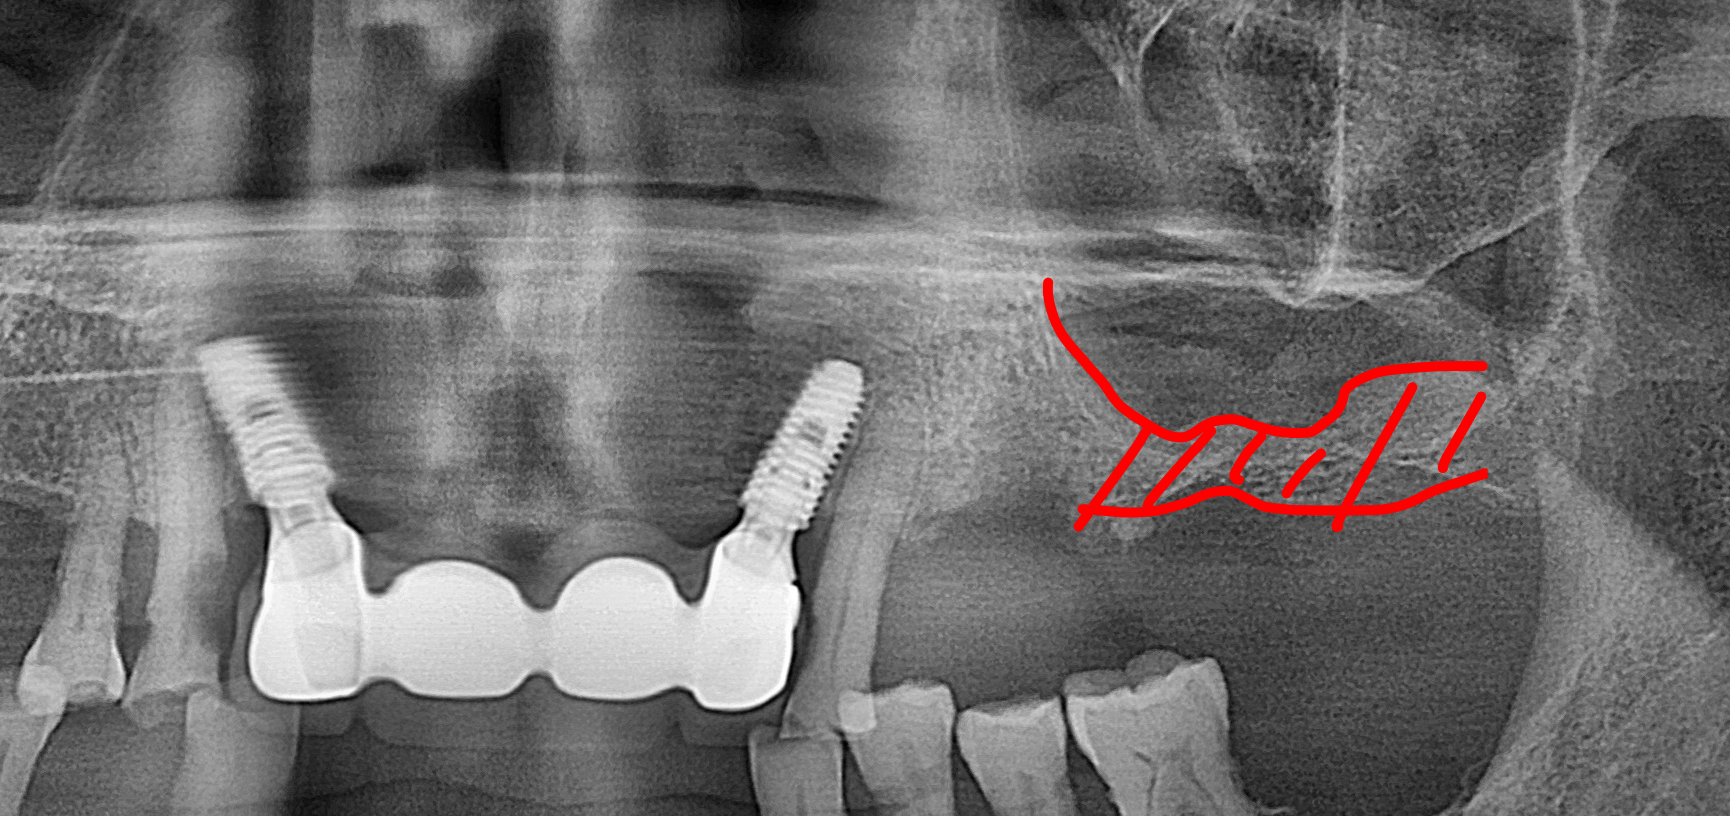

방사선 사진에서 확인할 수 있듯, 좌측 상악 어금니 부위는 치아가 빠진 지 오래되어 잔존 치조골(잇몸뼈)이 매우 얇아진 상태였습니다. 임플란트를 단단하게 고정할 뼈가 부족했기 때문에, 위턱뼈 속의 빈 공간인 상악동 막을 조심스럽게 들어 올리고 그 공간에 뼈를 채워 넣는 '상악동 거상술'을 시행했습니다.

수술의 효율성을 높이고 환자분의 내원 횟수를 줄이기 위해 상악동 거상술과 임플란트 픽스처 식립을 동시에 진행했습니다.